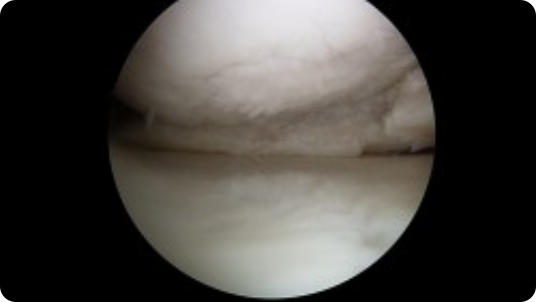

Arthroscopic image of an ACL tear Arthroscopic image of an ACL reconstruction

ACL Tear

ACL Reconstruction